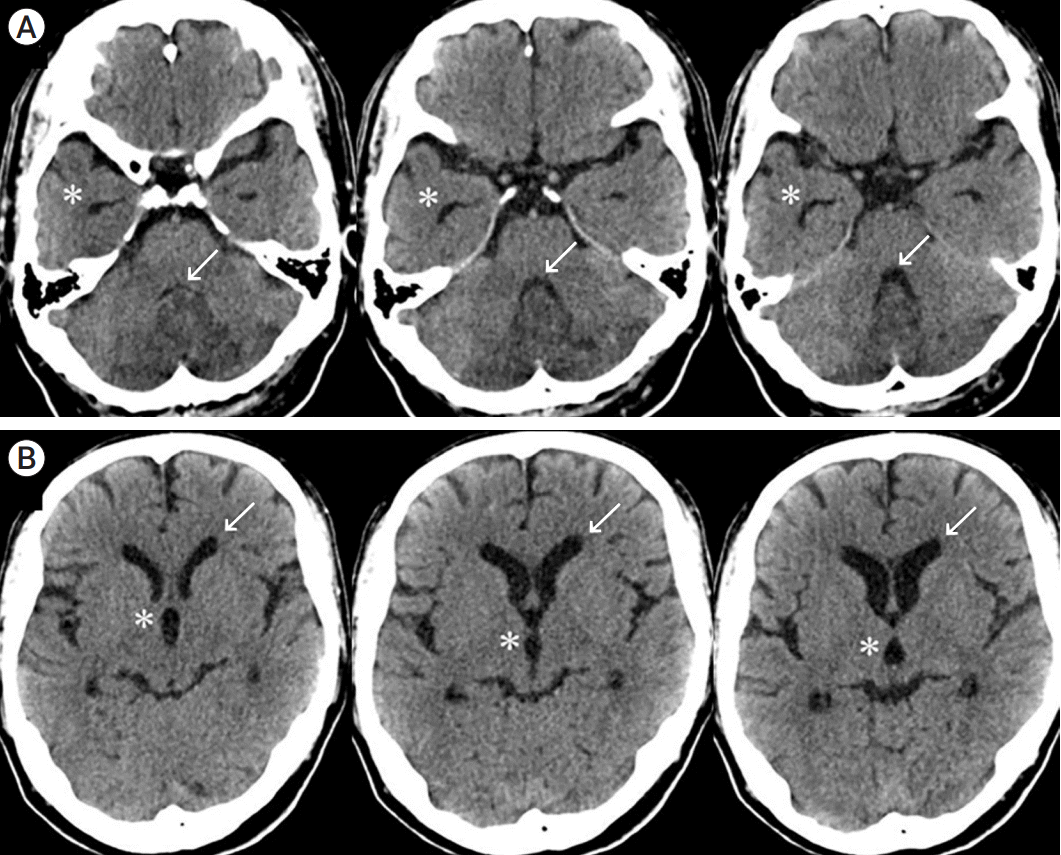

Fig. 2.

(A) Postoperative CT; the asterisk shows catheter insertion to allow the side hole to be located at the infarction site to the maximum extent possible. The arrow shows relaxation of the fourth ventricle compression. (B) CT shows improvement of the third ventricle dilatation (asterisks). The arrow shows reduction of the lateral ventricle anterior horn expansion. CT, computed tomography